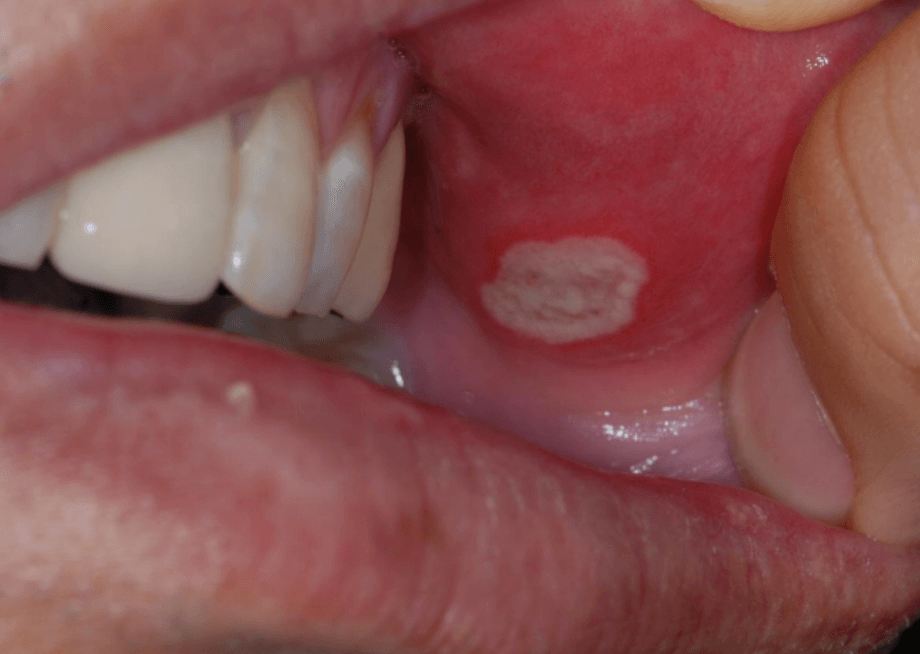

아프타성 구내염

가장 흔한 유형으로 작고 둥근 궤양이 입 안 점막, 혀, 잇몸 및 입천장에 발생합니다. 궤양의 주변에 붉고 염증이 나타나며 통증이 심합니다. 일반적으로 2주 안에 자연치유 되지만, 재발 가능성이 높습니다.